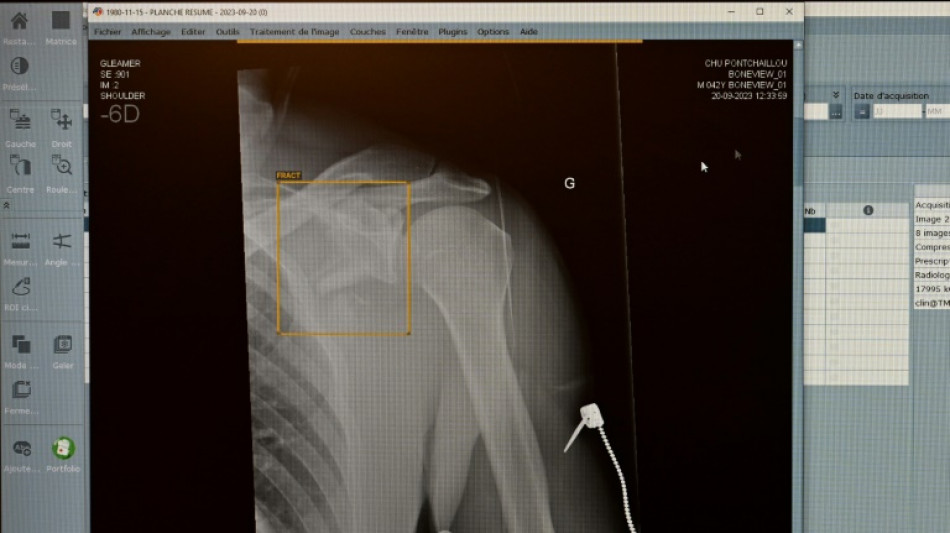

Jedes achte vom TÜV im vergangenen Jahr geprüfte medizinische Röntgengerät hat Mängel aufgewiesen. Die Gutachter stellten an 1893 der insgesamt rund 15.600 untersuchten Röntgengeräte Mängel wie etwa unzureichend gekennzeichnete Kontrollbereiche fest, wie der TÜV-Verband am Mittwoch in Berlin mitteilte. Die höchste Mängelquote wiesen Röntgengeräte in Zahnarztpraxen auf.

Die Mängelquote von Röntgengeräten in der Humanmedizin lag bei 13 Prozent und betraf etwa Bildwiedergabesysteme. Fehlerhafte Bildwiedergabesysteme gefährdeten die Diagnosesicherheit und könnten zu Fehldiagnosen oder unnötiger Strahlenbelastung führen. Die Mängelquote in der Veterinärmedizin lag ebenfalls bei 13 Prozent.